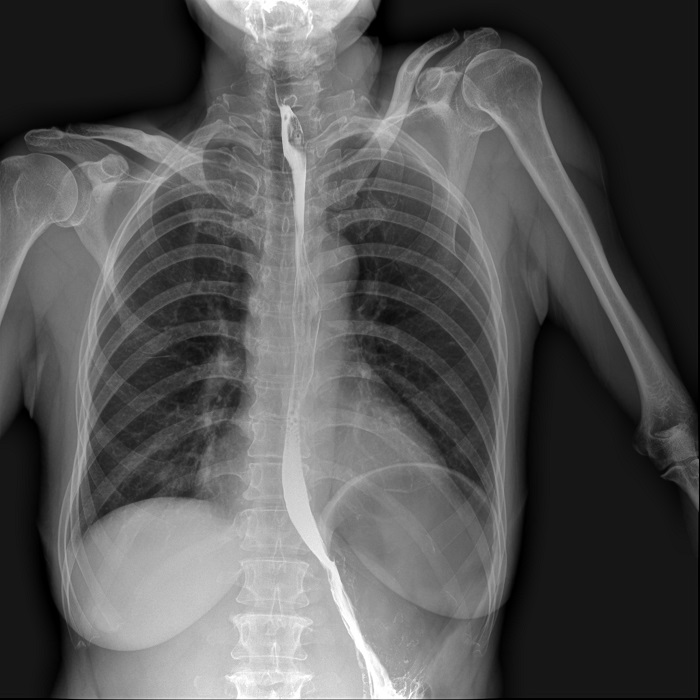

消化道造影高清影像圖片

普利德多功能懸吊動(dòng)態(tài)DR擁有17x17英寸成像幅面,在做消化道造影檢查時(shí),對(duì)于食道、胃、小腸、結(jié)腸等大范圍成像部位,可一次曝光完成;造影過程中,可以實(shí)現(xiàn)毫秒級(jí)動(dòng)靜態(tài)圖像切換,100μm高幀率動(dòng)態(tài)平板,1800萬像素高清點(diǎn)片,尤其在食道造影中優(yōu)勢(shì)明顯,可快速捕捉病變部位的影像,成像清晰而迅速,極大提升病灶檢查的檢出率,讓診斷更精準(zhǔn)。